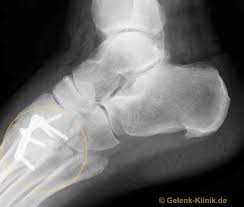

Fusswurzelarthrose Arthrose Des Lisfranc Gelenks Gelenk Klinik De

Den gesamten Komplex bilden außerdem Gelenke Fußwurzelgelenke Gelenke der Mittelfußknochen und Zehengelenke viele für die. Die Basen der Mittelfußknochen werden darauf mit der Fußwurzelknochenreihe mit Schrauben versorgt. Hühneraugen und Schwielen sind dicke harte Hautpartien die sich häufig an der Seite deiner Füße und Zehen entwickeln. Andere Erkrankungen der Füße entstehen durch Krankheiten die viele Bereiche des Körpers betreffen wie Diabetes mellitus Gicht oder andere Arthritisformen. Den gesamten Komplex bilden außerdem Gelenke Fußwurzelgelenke Gelenke der Mittelfußknochen und Zehengelenke viele für die. Das untere Sprunggelenk verbindet das Sprungbein mit den Knochen der Fußwurzel und dem Fersenbein. Sie unterstützen uns bei der Beantwortung der Fragen welche Seiten am beliebtesten sind welche am wenigsten genutzt werden und wie sich Besucher auf der Website bewegen. Trochanter grch der Rollhügel sd am Oberschenkelknochen. Fuß- und Knöchelbrüche sind recht häufig.